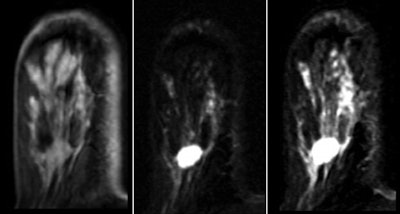

Overall, of the 108 lesions, 107 (99.1%) were correctly assessed as probably benign, for a negative predictive value of 99.1%. Histopathology was requested for 44 patients; 43 lesions (39.8%) were classified as benign and one (0.9%) as malignant. There were no changes evident in any of the remaining 64 (59.2%) lesions during the follow-up period, according to the authors.

Based on the findings, specific imaging features for BI-RADS 3 lesions at MRI -- such as round or oval shape, smooth or lobulated margins, and a type I or type II curve -- should be included in a new version of the BI-RADS lexicon, the team wrote.